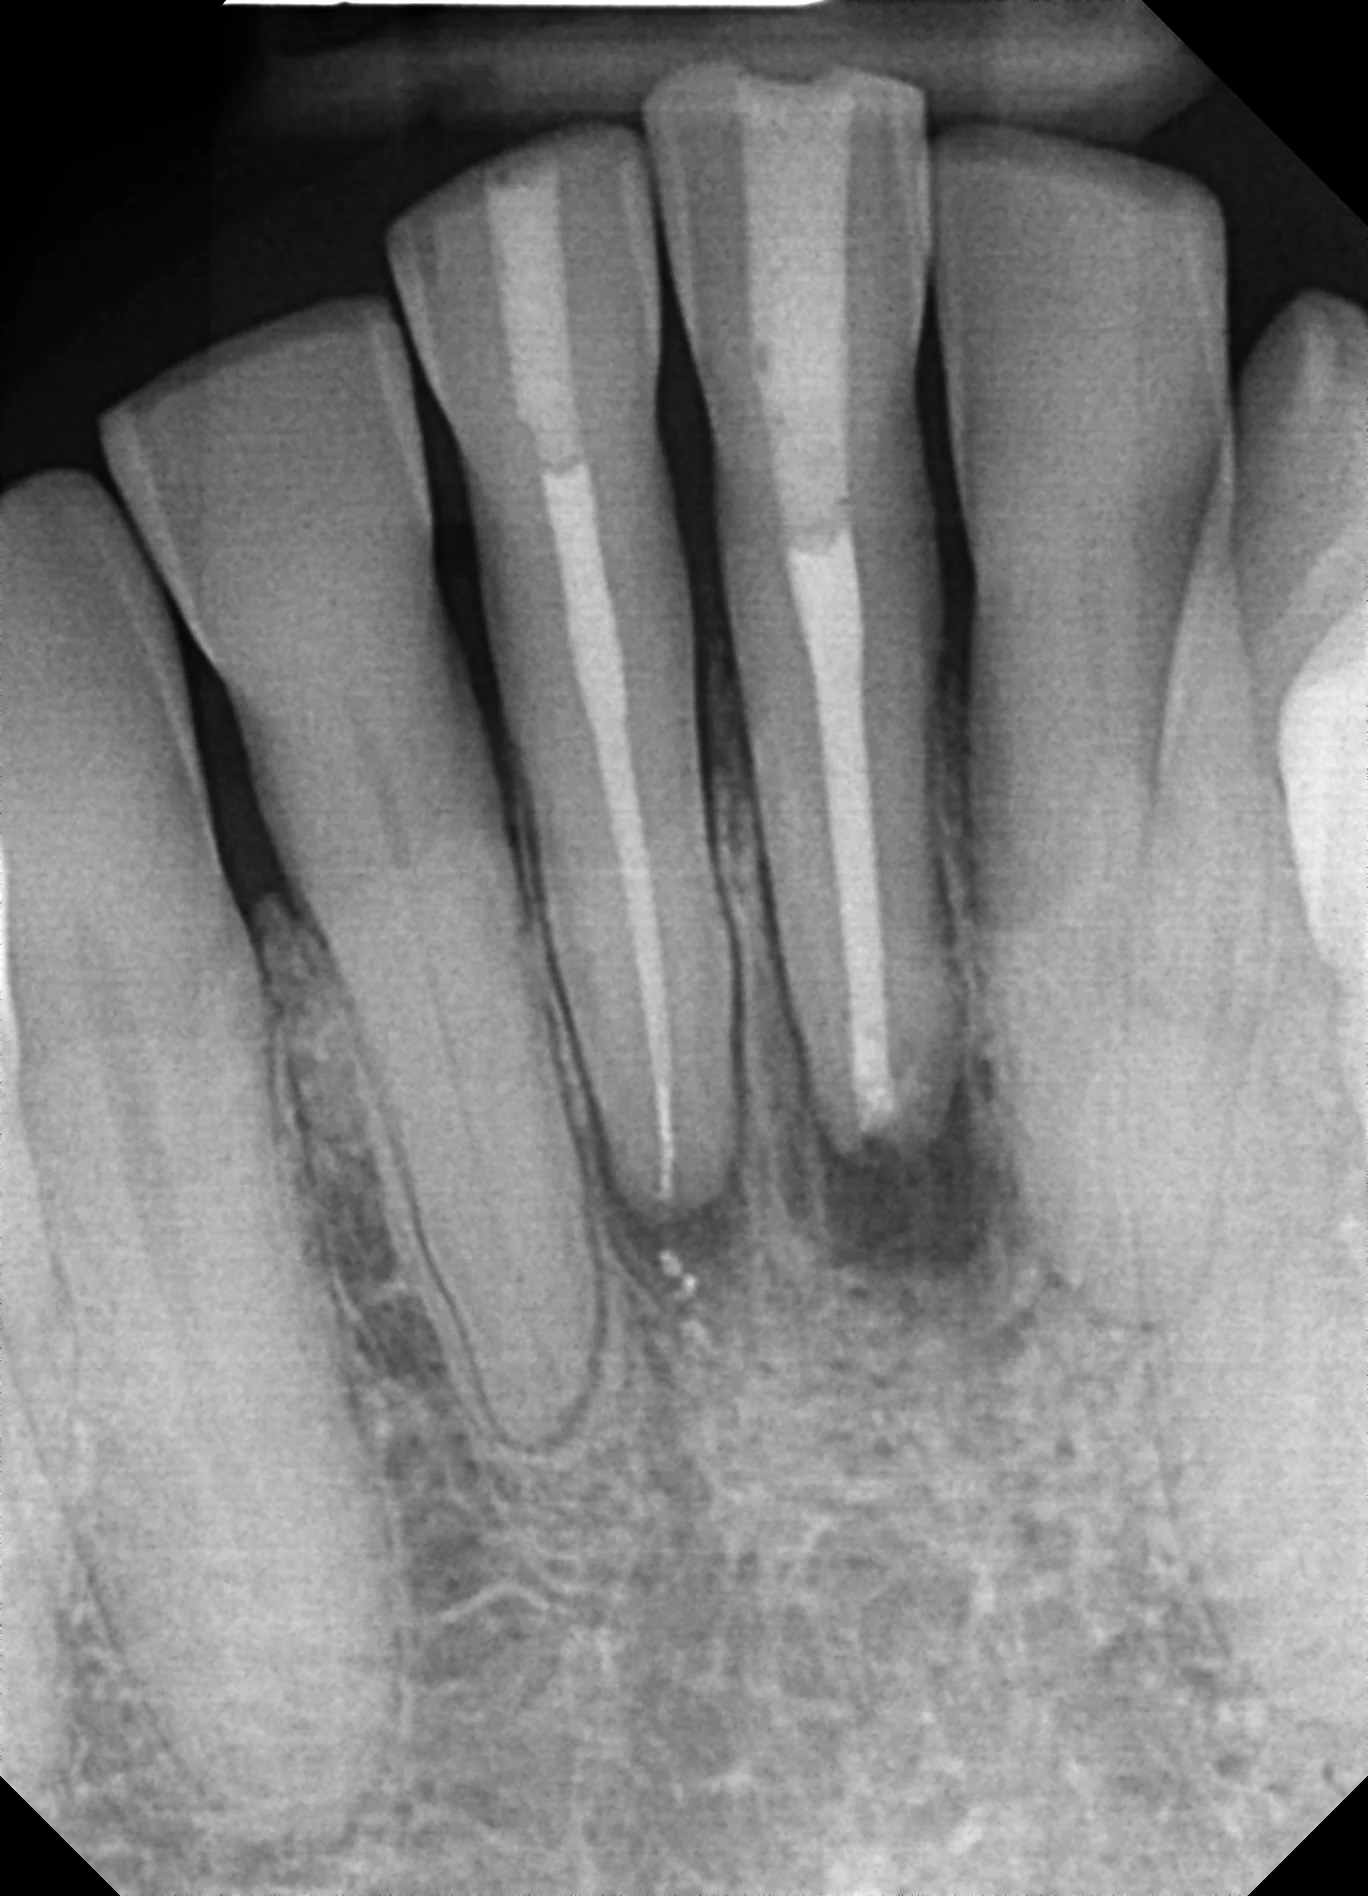

The referring dentist had completed root canal treatment on teeth #24 and #25 several months prior, but the patient returned with unresolved bite sensitivity and a draining sinus tract on the buccal gingiva. CBCT imaging revealed periapical radiolucency with thinning of the buccal cortical plate — findings that didn't fully explain why the canals appeared well-obturated.

We raised a full-thickness mucoperiosteal flap under local anesthesia to expose the root apices of both teeth. Under 16x microscope magnification, the root surfaces were inspected systematically.

• Key Finding: A vertical cemental tear extending 4-5mm along the root surface of #24, with a loose cementum fragment partially separated from the root.

• Granulation Tissue: Inflammatory tissue had infiltrated the tear defect, creating a pocket of chronic infection invisible on any radiograph.

Cemental tears are among the most difficult endodontic diagnoses because they don't appear on conventional periapical radiographs and often present identically to failed root canal treatment. Even CBCT can only suggest the possibility — definitive diagnosis requires direct surgical visualization.

• CBCT Pattern: Periapical radiolucency with buccal plate erosion in a well-treated tooth pointed to a surface-level defect rather than missed canal anatomy.